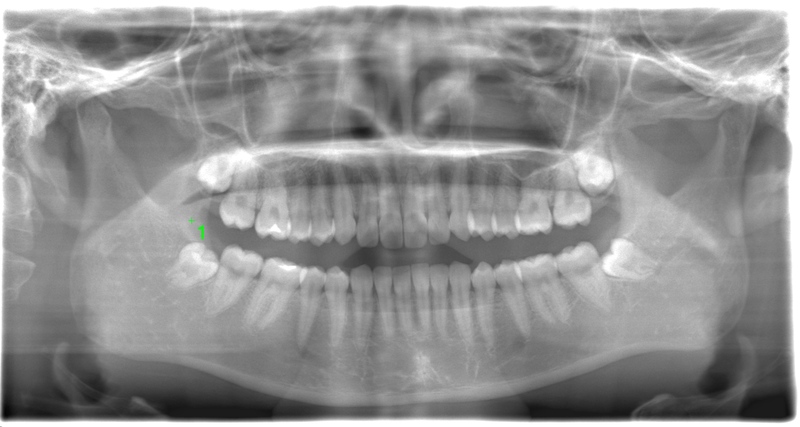

CASE 2

基本情報

| 年齢・性別 | 30代・男性 |

| 主訴 | 左上下親知らず抜きたい |

| 抜歯期間 | 30分 |

| 抜歯費用 | 約2,500円(保険内) 別途CT撮影で3,000円 |

| 抜歯内容 | 左上下の親知らず抜歯 |